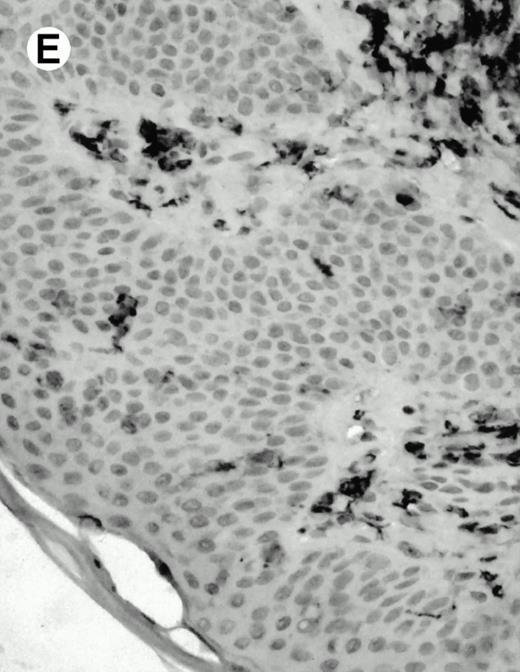

Both paraffin-embedded tissues and frozen sections (with or without heat antigen retrieval) were prepared for immunohistology as described in Materials and Methods. KPL1 stained numerous T cells in the T-zone (TZ) of a human tonsil (Fig 8A), but did not stain B cells in the mantle zone (M) or germinal center (GC) of the secondary follicles. Macrophages in the germinal center stained but follicular dendritic cells did not (Fig 8A). Just outside the germinal center, intense KPL1 staining of overlying plasma cells was observed. A high-power magnification (Fig 8B) shows this intense staining of plasma cells which surround the germinal centers. Subepithelial plasma cells also stained with KPL1 (data not shown), as did plasma cells around vessels in the skin (Fig 8C); these plasma cells costained with the plasma cell marker VS38 (Fig 8D). Thus, B cells located in germinal centers either lack the KPL1 epitope, or express it at levels which are not detected by these methods, whereas plasma cells in numerous sites express high levels. Similarly, four IL-6–dependent human myeloma cell lines expressed high levels of the KPL1 epitope (Diane Jelinek, personal communication, March 1997). Both cortical and medullary lymphocytes in the thymus stained with KPL1 (data not shown). Langerhans cells, bone marrow–derived antigen presenting cells which reside in the suprabasilar region of the epidermis, were also positive for KPL1 (Fig 8E). Langerhans cells in the tonsillar epithelium also stained with KPL1 (data not shown). Langerhans cells in soft tissue also stain with both KPL1 (Fig 8F) and CD1a (Fig 8G).

(E) Paraffin section of skin stained with KPL1. The Langerhans cells in epidermis and superficial dermis stain intensely in this example of Langerhans cell histiocytosis. The stained dendritic processes are apparent in the epidermis. (F) Langerhans cells in soft tissues also stain with KPL1. (G) Identification of Langerhans cells in (F) is confirmed by costaining with CD1a (immunoperoxidase with hematoxylin counterstain).